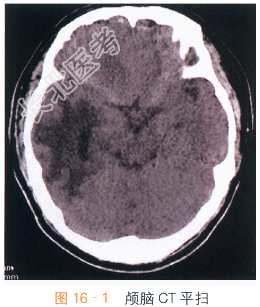

影像学资料如图16-1、图16-2所示。

颅脑平扫加强化MRI检查显示:右侧额叶及右颞枕叶见一长T₁等长T₂异常信号,注入对比剂后呈明显不均质强化,中间呈坏死性不强化改变。病变强化后边界不清,病变定位脑内,非硬脑膜起源,未见脑膜尾征。周围脑组织可见血管源性水肿征象,累及皮质下和深部白质。MRI检查显示较CT扫描清晰、明显。结合患者临床表现,考虑患者为转移瘤。